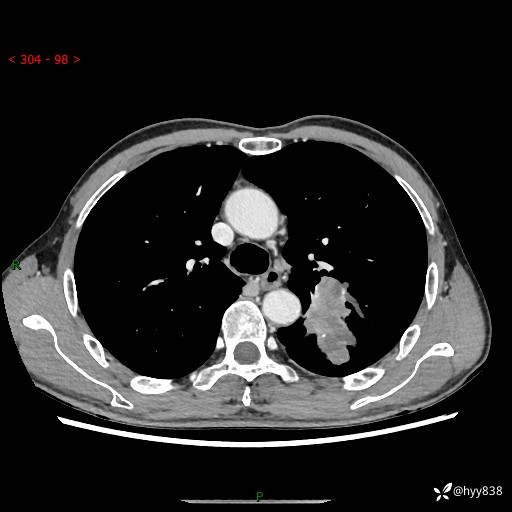

现病史:患者余4月前发现咳嗽咳痰伴痰中带血,无胸闷、胸痛、头晕、恶心、呕吐等不适,2天前因体检发现肺部结节遂于当地市第一人民医院行胸部CT薄层平扫+三维重建示:1.左肺上叶尖后段占位性病变考虑肿瘤性病变伴阻塞性肺炎,右肺上叶后段磨玻璃结节。2.肝内多发囊性灶、左肾结石。现患者为求进一步治疗,于我院门诊就诊,门诊以“肺结节”收入院。 自患病以来,精神、饮食、睡眠尚可,大小便正常,体力体重无明显减轻。

胸部CT增强扫描(外院平扫)